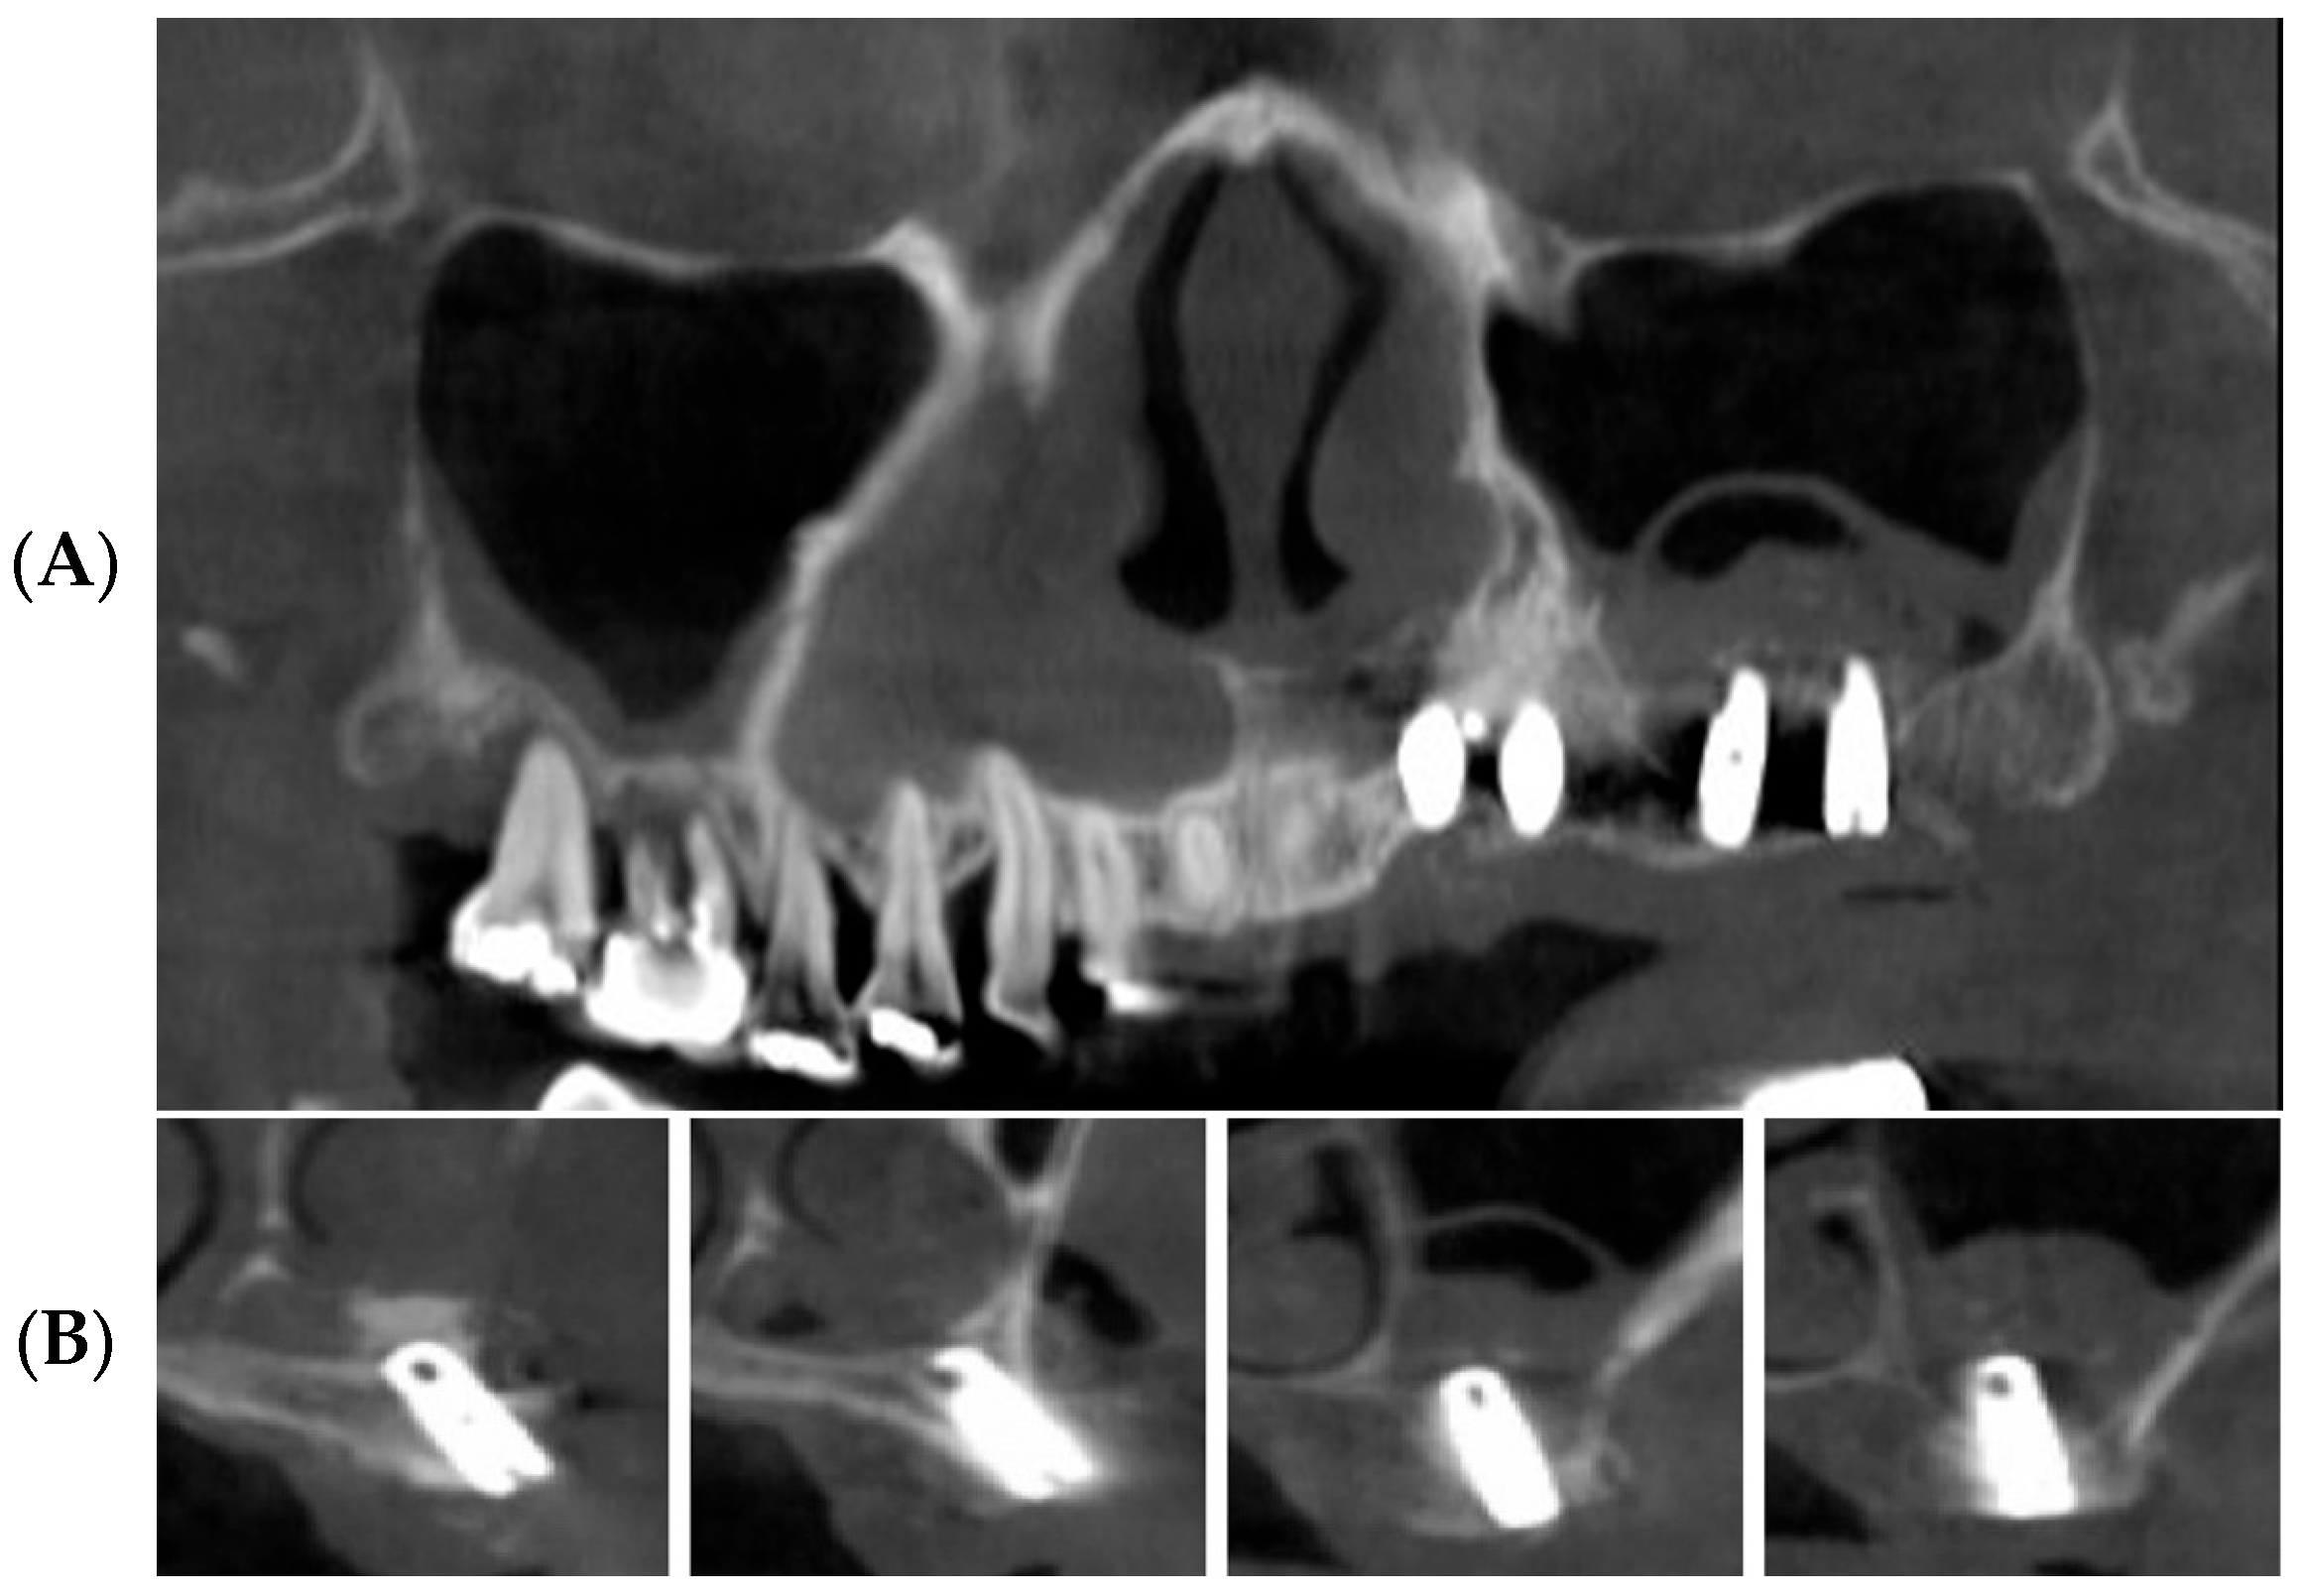

3.1. Clinical Results

3.2. Radiographic Results